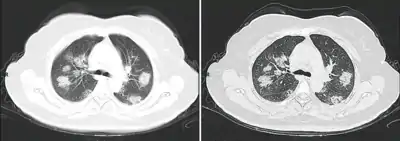

Dégâts pulmonaires

Les études en microscopie électronique et sur coupes histologiques de tissus pulmonaires (faites après autopsies) ont montré que les virions sont dans le poumon essentiellement localisés dans les pneumocytes[200].

Comme dans le cas du SARS, puis du MERS, la Covid se traduit dans l'arbre respiratoire par des lésions alvéolaires diffuses, caractérisées par des phases exsudatives et prolifératives de ces lésions, avec une congestion des vaisseaux capillaires et une nécrose systématique des pneumocytes, et très souvent une atteinte des membranes hyalines, un œdème interstitiel et intra-alvéolaire.

Les autopsies ont aussi révélé de fréquents événements thromboemboliques (« parfois cliniquement insoupçonnés au décès »)[201]. Outre une hyperplasie pneumocytaire de type 2, on a souvent observé une métaplasie squameuse avec atypie et micro-thrombus plaquettaire-fibrine[200],[202],[203],[204],[205].

L'infiltrat inflammatoire est toujours majoritairement composé de macrophages, souvent présents dans la lumière alvéolaire, souvent accompagnés de lymphocytes dans l'interstitium[200]. Des membranes hyalines se forment fréquemment, et une hyperplasie atypique des pneumocytes est également fréquemment constatée post-mortem. Le thrombus plaquettaire-fibrine des petits vaisseaux artériels peut être relié à une coagulopathie apparemment fréquente chez les malades de Covid-19 et qui selon Carsana & al (2020) devrait être l'une des principales cibles du traitement[200].